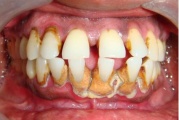

Krooniline parodontiit

Krooniline parodontiit on mikroobide poolt põhjustatud hammaste tugikudede põletik, mille tulemusena tekib progresseeruv alveolaarluu (nähtav röntgenograamil) ja periodontaalligamendi destruktsioon, igemetaskute moodustumine, igeme retsessioon või mõlemad kahjustused kombineeritult. Loe edasi »

Sümptomid:

- igemed veritsevad (19)

- igemed punetavad (21)

- ige on paistes (mädapunn)

- igemed on tursunud/vohavad (17)

- igemed on valulikud (19)

- igemepiir on taandunud (3)

- luu destruktsioon (5)

- puudulik suuhügieen (5)

- igemepealne hambakivi (5)

- igemealune hambakivi (4)

- halb hingeõhk / suu haiseb (12)